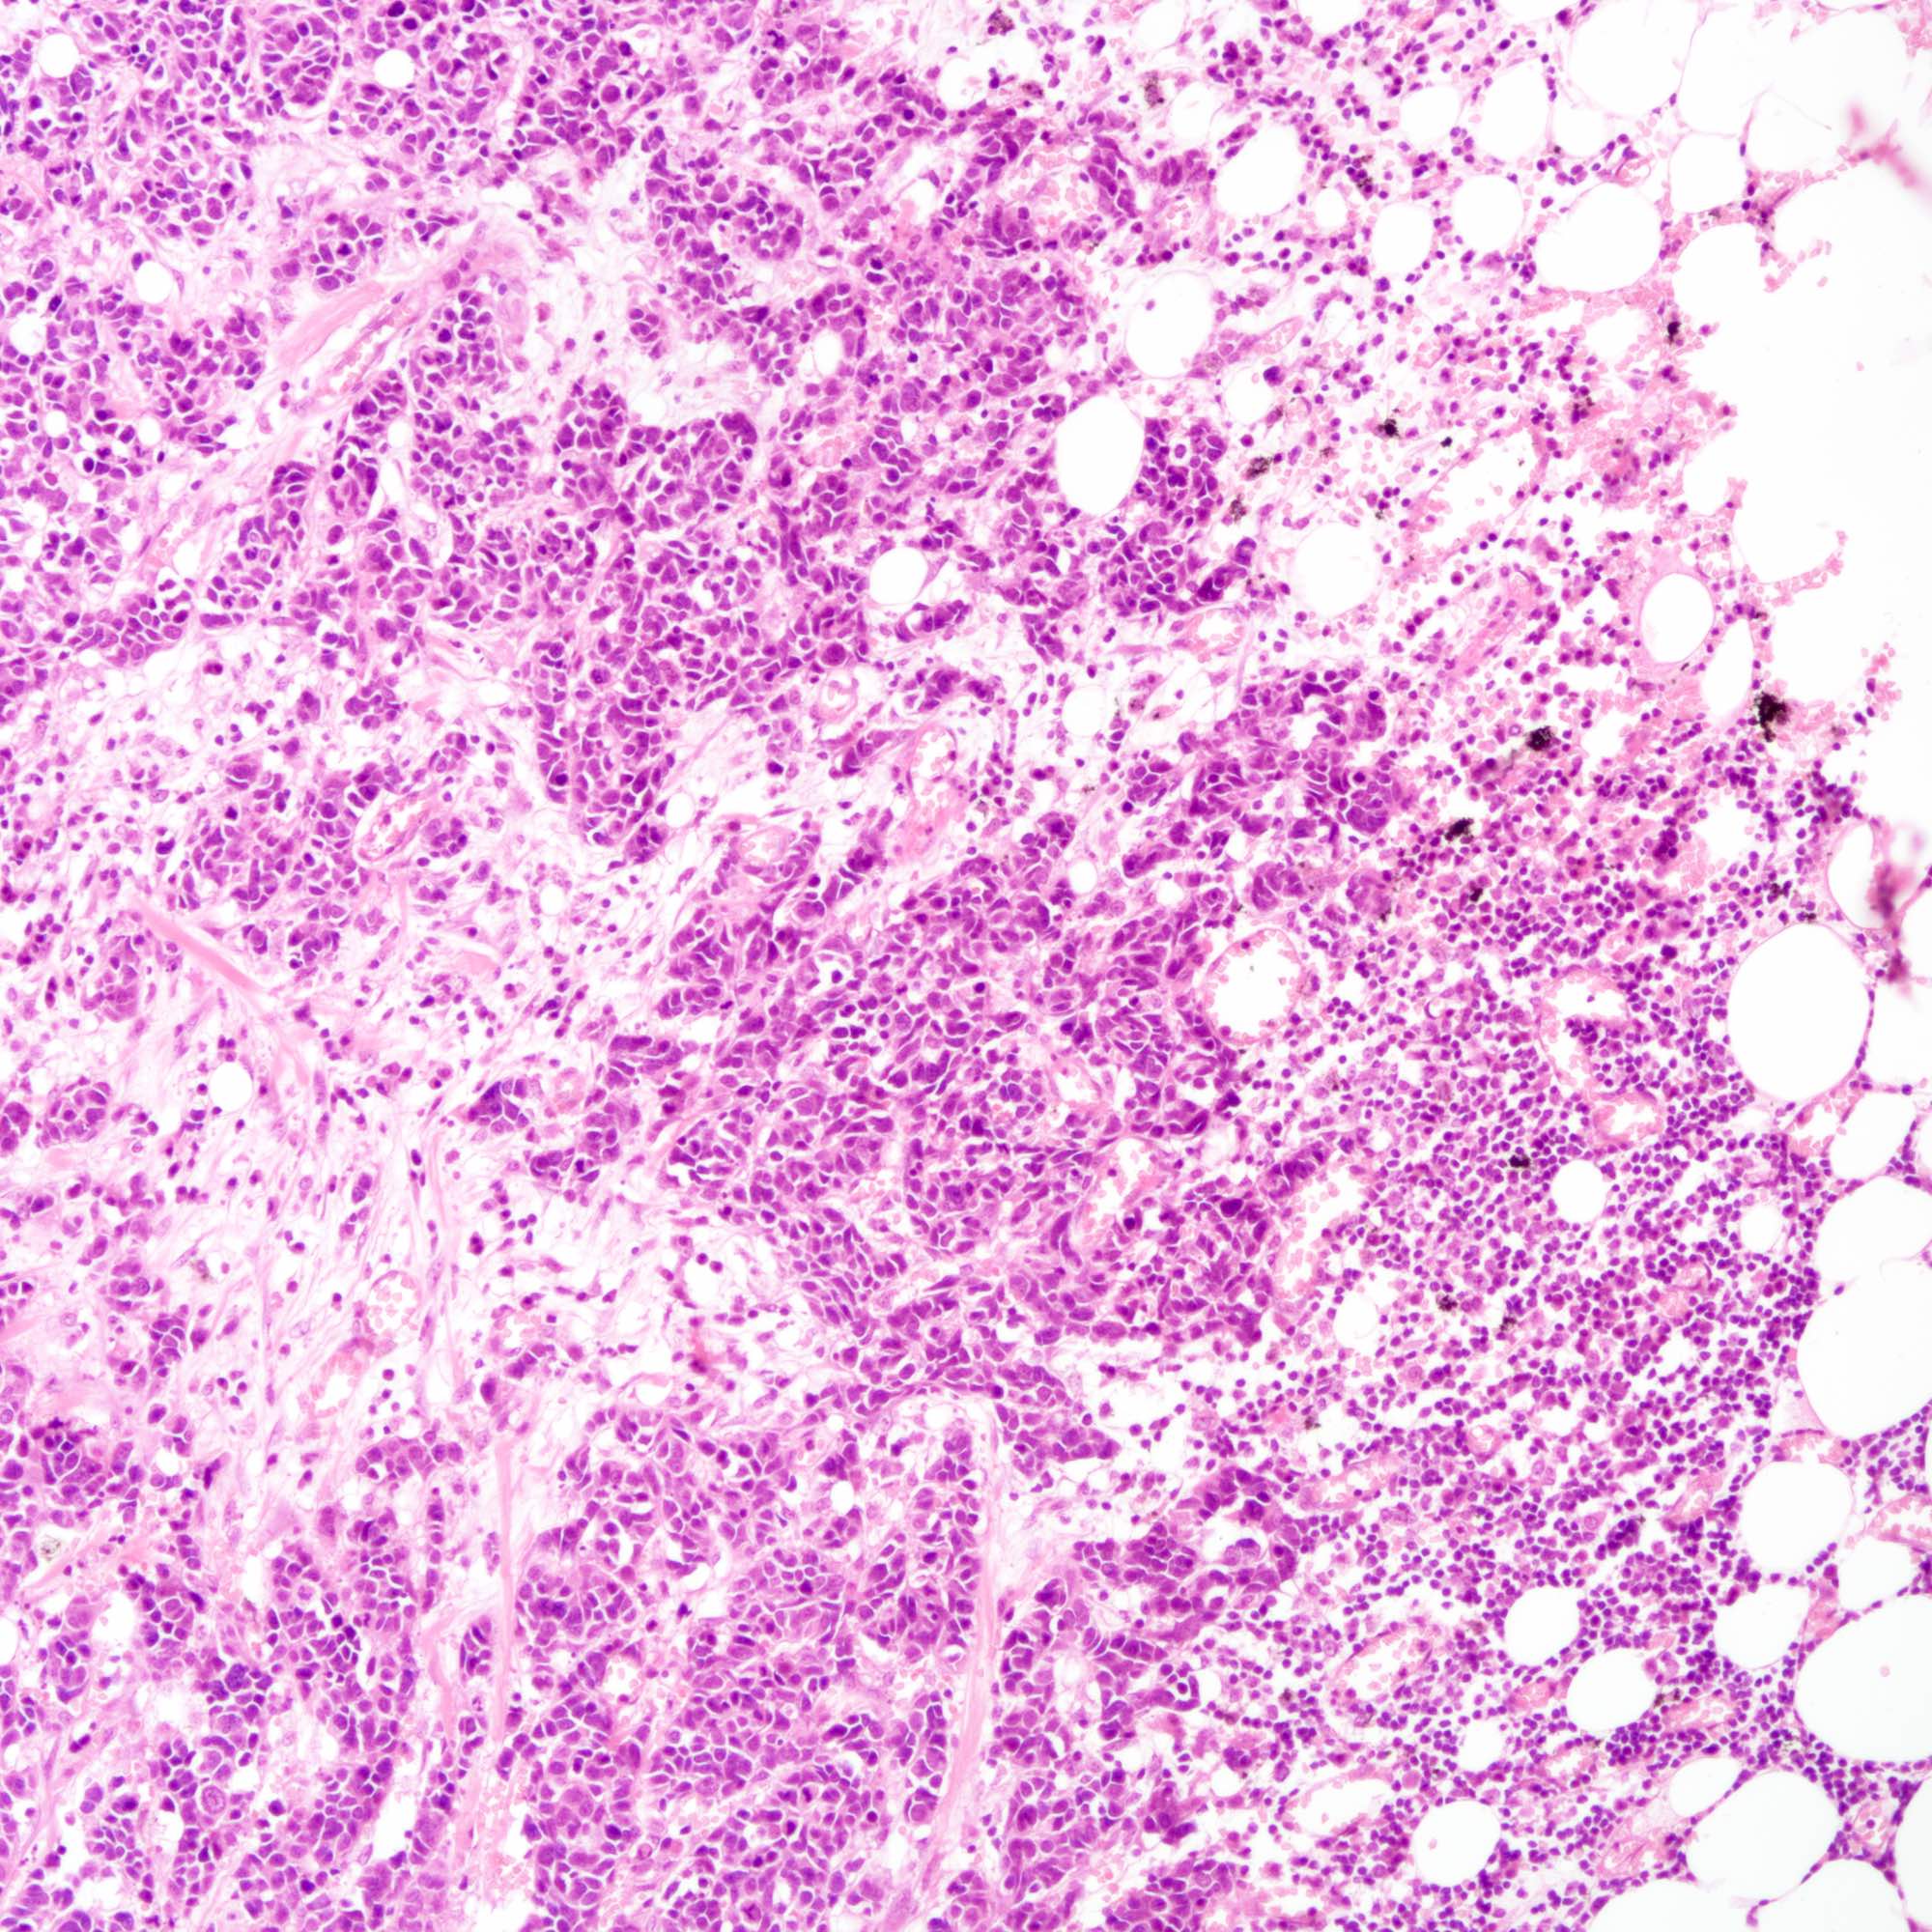

Contributed by Joshua J.X. Li, M.B.Ch.B., Gary M. Tse, M.B.B.S. and Kristen E. Muller D.O.

Small cell carcinoma

Microscopic (histologic) description

- Small cell carcinoma:

- Infiltrative growth pattern

- Crush artifact frequent

- Necrosis and lymphovascular invasion common

- Tumor cells densely packed with ill defined cell borders

- High N/C ratio with scanty cytoplasm

- Small dark hyperchromatic nuclei and inconspicuous nucleoli

- Mitotic count high

- Associated with proliferative changes, in situ carcinomas and invasive carcinomas (Am J Surg Pathol 2000;24:1231)

- In situ small cell carcinoma present in 5 out of 9 cases in a case series

- In situ / invasive ductal, lobular and squamous neoplastic components occasionally identified

- Infiltrative growth pattern